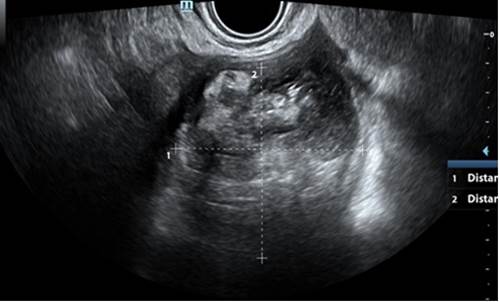

La evaluación ecográfica reportó el útero sin patología. En ovario derecho: se evidenció imagen ecomixta, predominantemente sólida, redondeada, de bordes regulares de 67 x 64 mm, con áreas hiperecogénicas centrales (Figura 1), score doppler 2, sugestiva de teratoma. En ovario izquierdo: se evidenció imagen multilocular ovalada, anecoica (vidrio esmerilado), con tabique completo de 2 mm, paredes internas lisas, bordes regulares, de 67 x 42 mm (Figura 2), score doppler 1.

Figura 1 Ovario derecho con imagen ecomixta, predominantemente sólida, redondeada, bordes regulares de 67 x 64 mm.